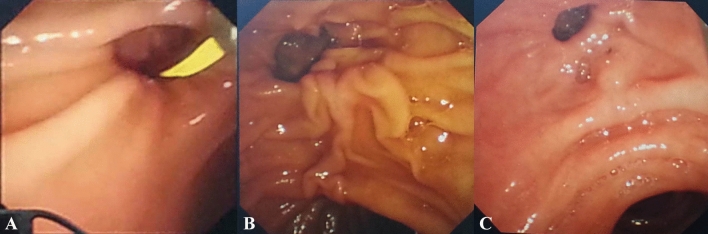

Patients with CBD stones, treated by ERCP in our hospital from January 2015 to December 2018, were retrospectively reviewed. Patients’ exclusion criteria were any of the following: history of EST, surgical history involving the gastrointestinal tract, co-existing bile leakage, choledochoduodenal fistula, severe bleeding tendency, concomitant pancreatic or biliary malignant disorders. According to the presence of PAD, the patients were divided into a PAD group and a non-PAD group. PAD was sub-classified under two types based on the locations of the major papilla: type A, where the papilla was located outside the diverticula or at the margin of the diverticula, and type B, where the papilla was located inside the diverticula11 (Fig. 1). The study was executed according to the Helsinki Declaration and followed the local legislation and was approved by the Ethics Committee of First Hospital affiliated to Dalian Medical University. All the patients or their relatives presented written informed consent before the procedure.

Some procedures were accomplished under ECG monitoring. Tetracaine was used for local anesthesia of the pharynx. The patients were sedated and given pain relievers via intramuscular injection of diazepam (5 mg) and meperidine (50 mg). Administrations of 20 mg of butyl scopolamine bromide were given intramuscularly prior to the procedure to inhibit duodenal peristalsis. All these procedures were performed by experienced endoscopists at a single center with side-viewing endoscopes (JF-260; Olympus Optical Corporation, Tokyo, Japan) (Figs. 2, 3).